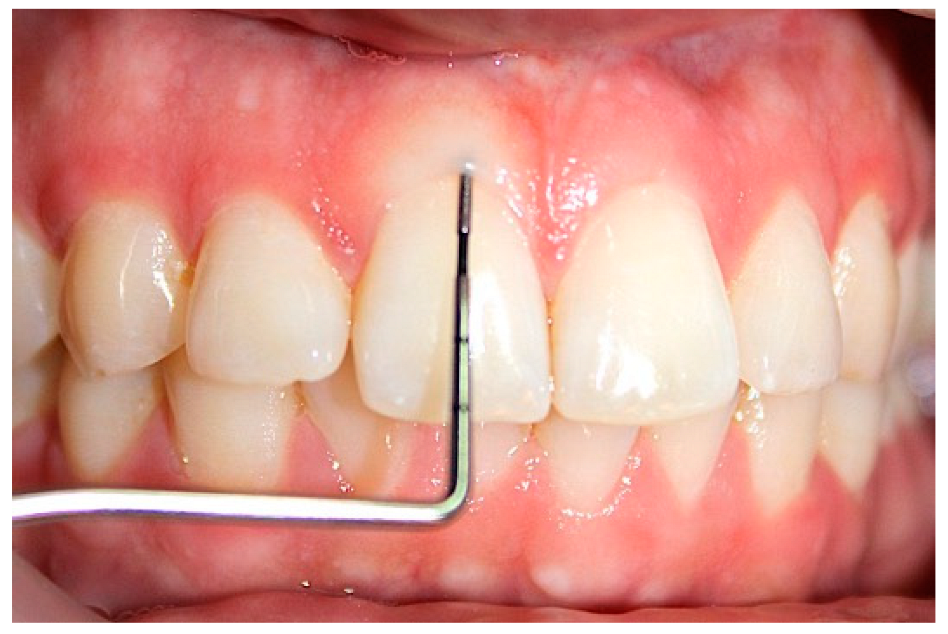

2.1. Clinical Examination